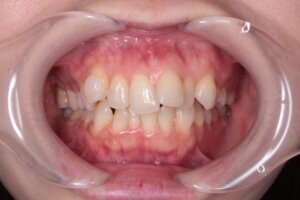

矯正前の患者さんの口元のお写真です。

「前歯のデコボコが気になる」ということで来院されました。

確かに、上下共に、歯が重なってしまっていで歯並びがデコボコしています。